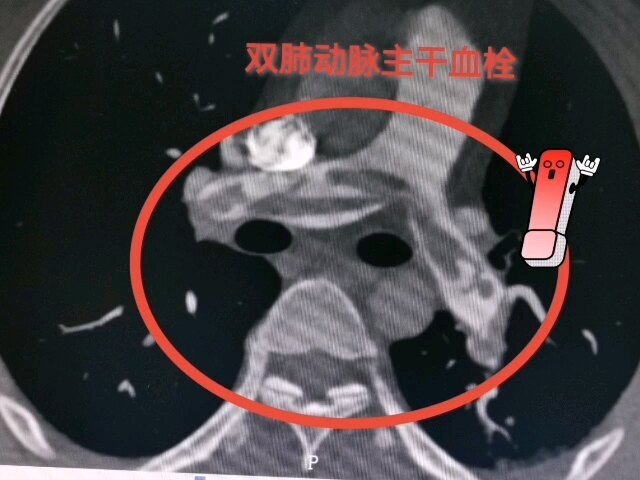

确诊肺栓塞一例

李刚主治医师 澄城县医院 心血管内科